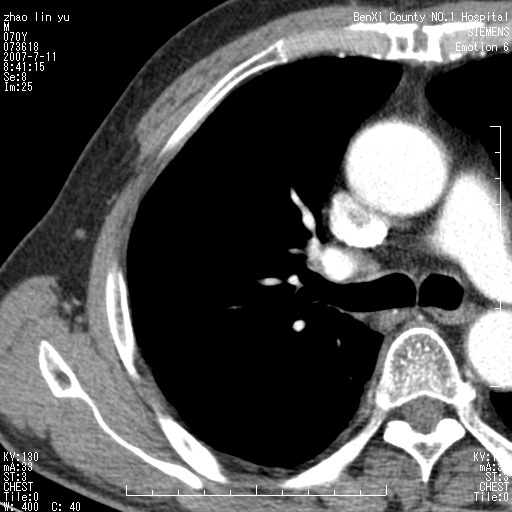

以下是引用王靖旗在2007-7-10 17:12:00的发言:[br] 男、70、咳嗽两个月,半年前换瓣手术,胸片未见异常,于昨天行x片发现右肺上野大片影,行ct扫描,这里是减薄图像,余肺正常。明天晚上会有增强扫描片,到时我会上传。[br][br] 冠状位请大家细看,应该是有意义的,[br][br] 请大家先看平扫发表意见。[br][br]

以下是引用zhangzhongshou在2007-7-10 21:43:00的发言:[br]右肺上叶周围型肺癌,以孤立型细支气管肺泡癌可能性大。